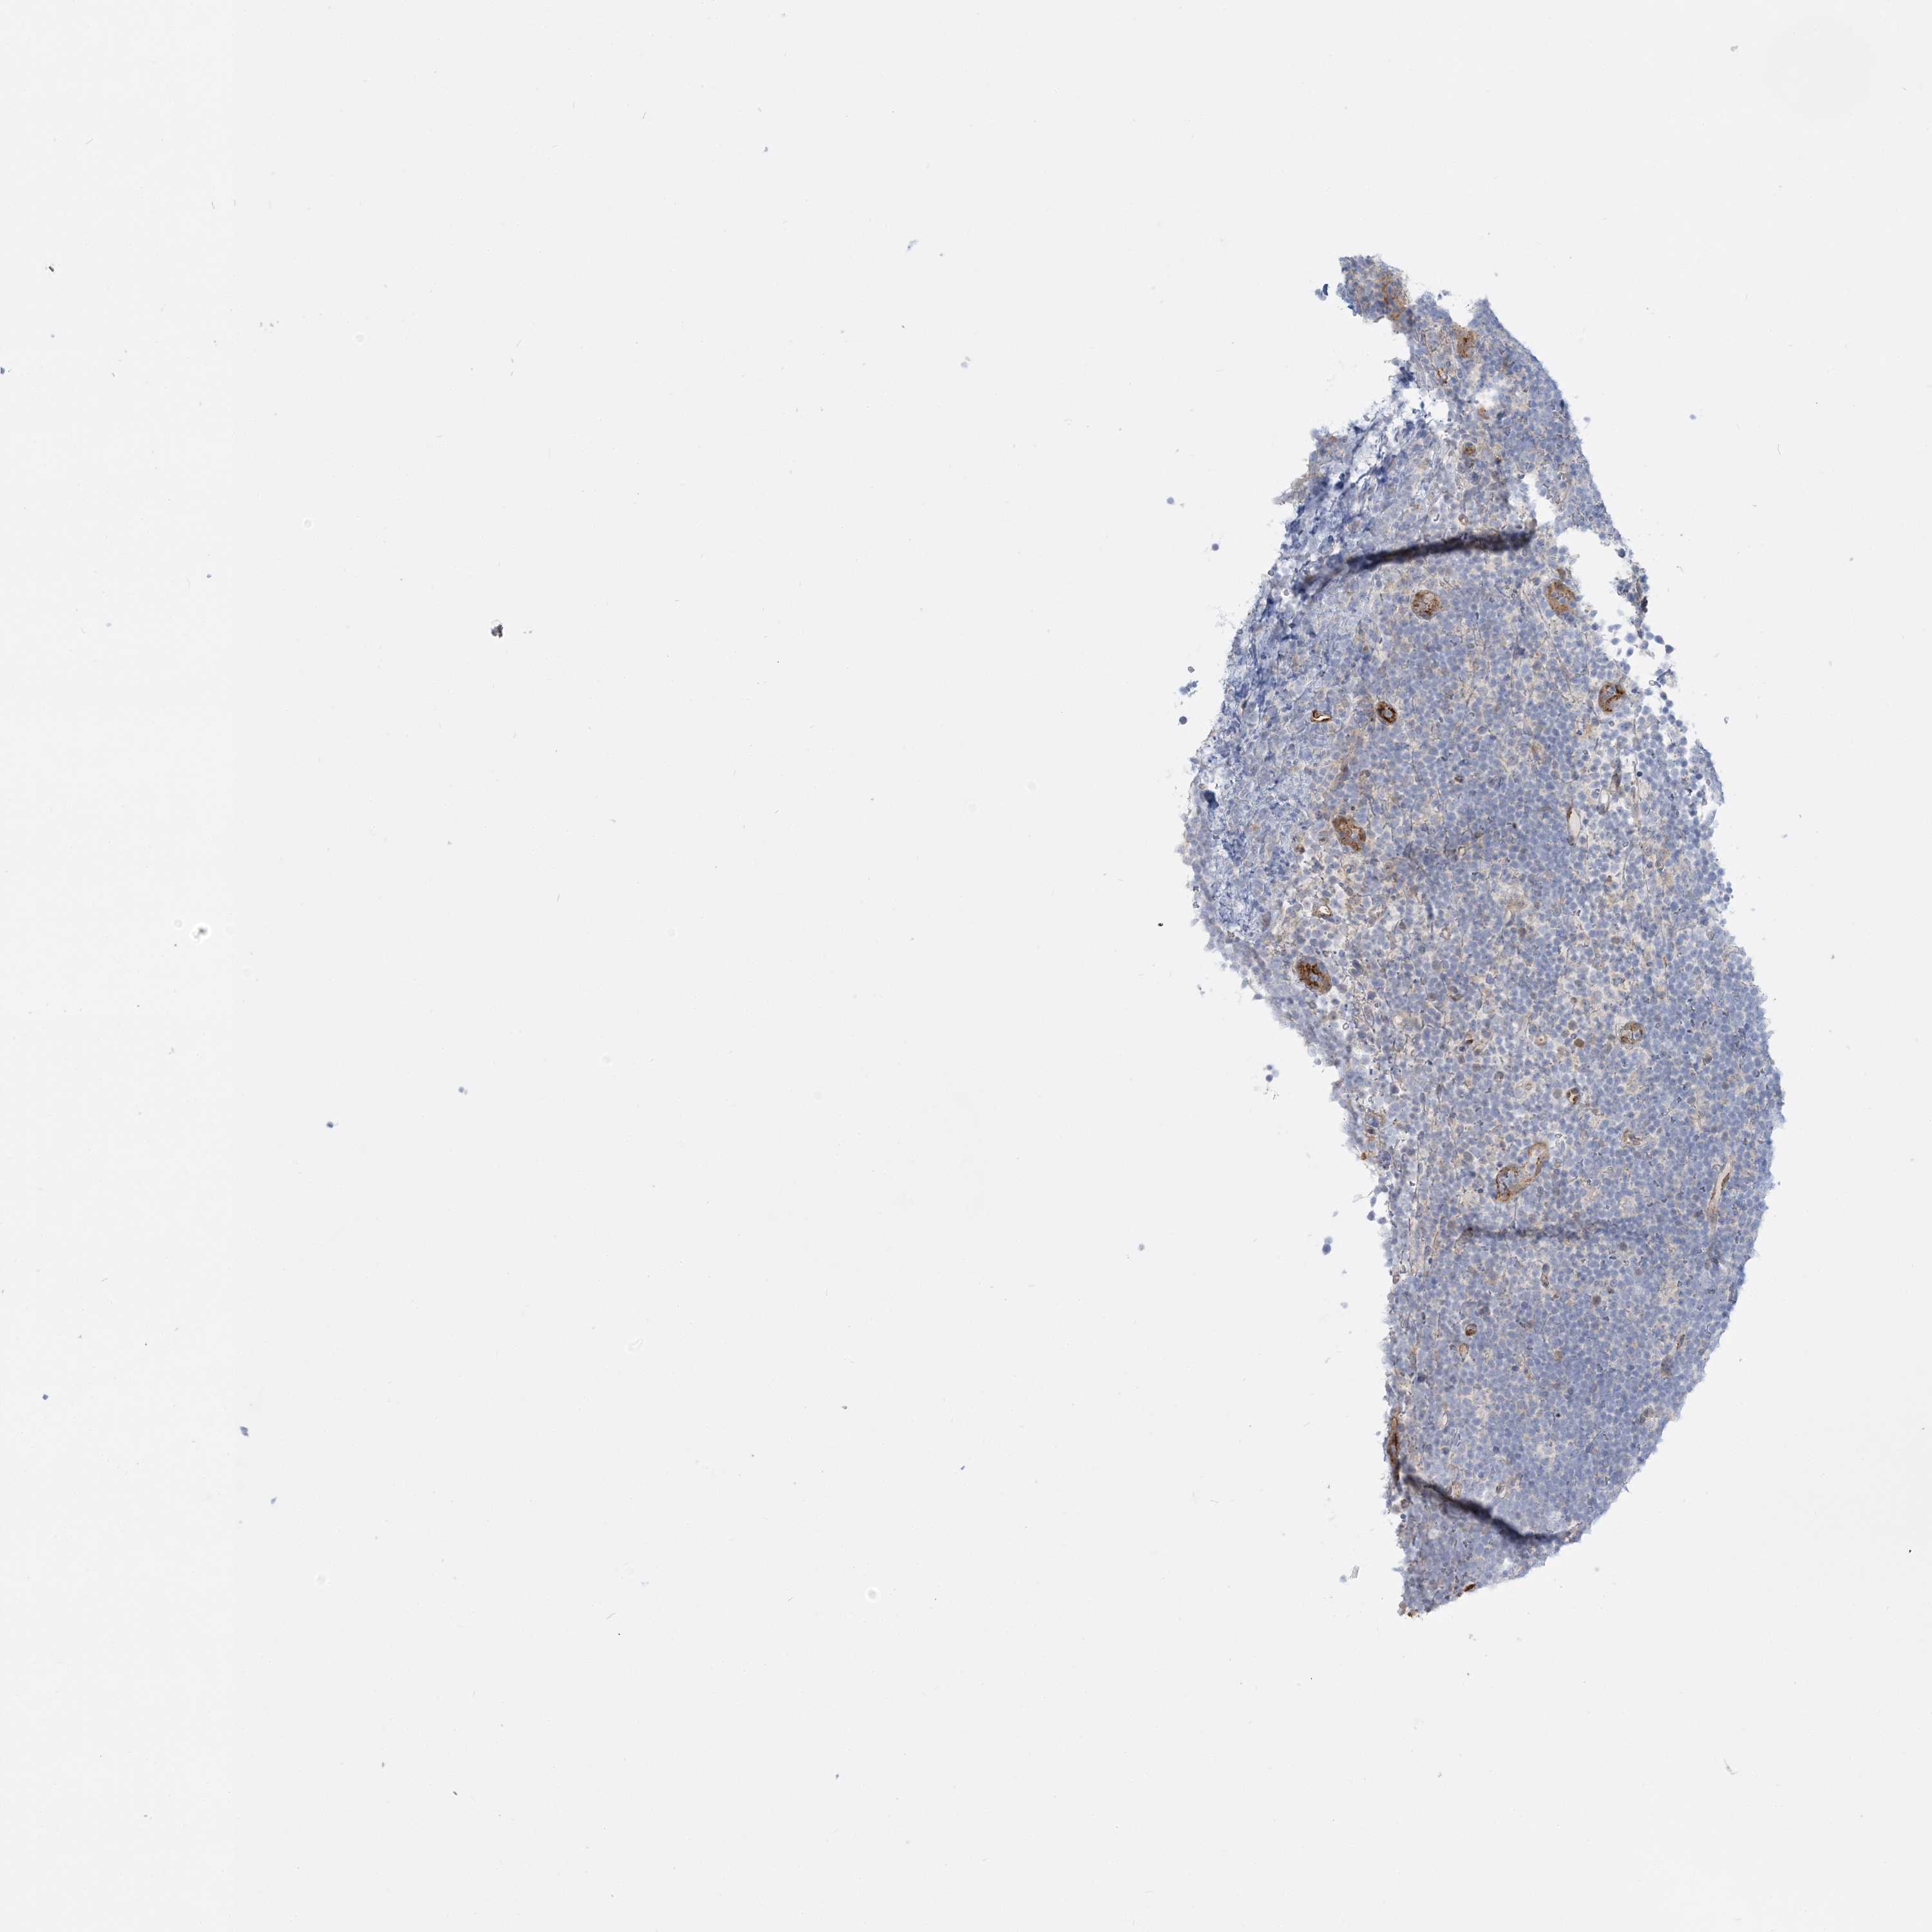

CANCER LYMPHOMA Show tissue menu

LYMPHOMA - Protein expressioni

A mouse-over function shows sample information and annotation data. Click on an image to view it in a full screen mode. Samples can be filtered based on level of antibody staining by selecting one or several of the following categories: high, medium, low and not detected. The assay and annotation is described here.

Each image is clickable and will lead to virtual microscopy that enables deeper exploration of all samples and also displays staining intensity scores, fraction scores and subcellular localization as well as patient and tissue information for each sample.

Antibody HPA036698

Antibody HPA036699

Hodgkin's disease, NOS

Malignant lymphoma, non-Hodgkin's type, High grade

Malignant lymphoma, non-Hodgkin's type, Low grade